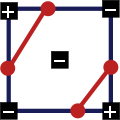

Давайте взглянем на схему:

Для обнаружения границ сосуда используется классический подход (edge detection by gradient) совместно с поиском пути. Схема: